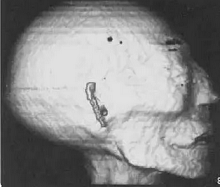

CT image of the mummy's head

In 1988, using a portable CT scanner, research altered many of the conclusions from the earlier exam: the mummy was most likely 30 to 40 years old when she died, and she stood only 5 feet 2 inches tall.

In 2014, new CT scans were made of the mummy. It turned out that the occupant of Wenuhotep's sarcophagus was not even female. The male un-named occupant was mummified, and the accompanying decoration applied outside of the mummy’s wrappings, showed that he lived during the Ptolemaic Period, about 332–30 BC.